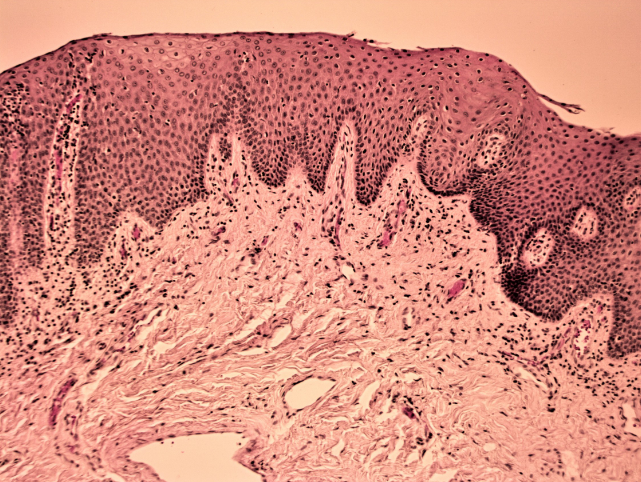

Stratified squamous epithelium (keratinized)

A multi-layered epithelium composed of flattened cells, providing protection against abrasion and found in areas such as the skin and mucous membranes.

<p>A multi-layered epithelium composed of flattened cells, providing protection against abrasion and found in areas such as the skin and mucous membranes. </p>